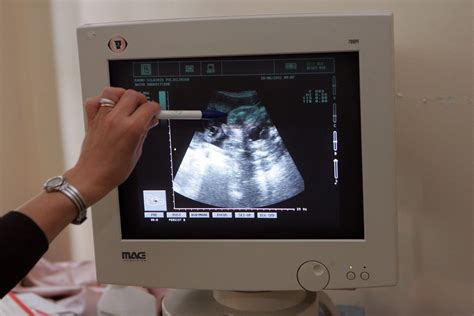

Ultragarsinis tyrimas, dažniau vadinamas tiesiog echoskopija, yra neinvazinis ir vienas pagrindinių tyrimų nėštumo metu, leidžiantis įvertinti vaisiaus raidą, augimą ir būklę, ar nėra jokių nukrypimų nuo įprastos nėštumo eigos.

Ultragarsinis tyrimas dažniausiai atliekamas transabdominaliniu būdu, per nėščiosios pilvo sieną.

BŪTINIEJI TYRIMAI. Ultragarso tyrimas pagal Lietuvos Respublikos sveikatos apsaugos ministro įsakymą, būtinai atliekamas du kartus: 11-14 ir 18-20 nėštumo savaitę. Per pilvo sienelę, dažniausiai įprastiniu 2D echoskopu gydymo įstaigose. Vertinama placenta, vaisiaus dydis ir būklė (galima smulkiai apžiūrėti vaisiaus vidaus organus), judesiai, vandenų kiekis. Šiuo laiku tiksliausiai pasakoma, ar nėra apsigimimo, ar vidaus organų struktūra normali, kokia vaisiaus lytis.

Ultragarsinio tyrimo metu gydytojas akušeris ginekologas, tirdamas echoskopu, įvertins, kiek yra vaisių, kiek yra jų vandenų, pasakys, kur yra įsitvirtinusi placenta. Gydytojas taip pat įvertins vaisiaus anatomiją ir pamatuos patį vaisių.

Tyrimo metu ant tiriamos vietos išspaudžiama specialios želė. Želė reikalinga tam, kad nesusidarytų oro tarpo tarp paciento odos ir echoskopo daviklio. Tokiu būdu perduodamas tikslesnis vaizdas į kompiuterio ekraną.